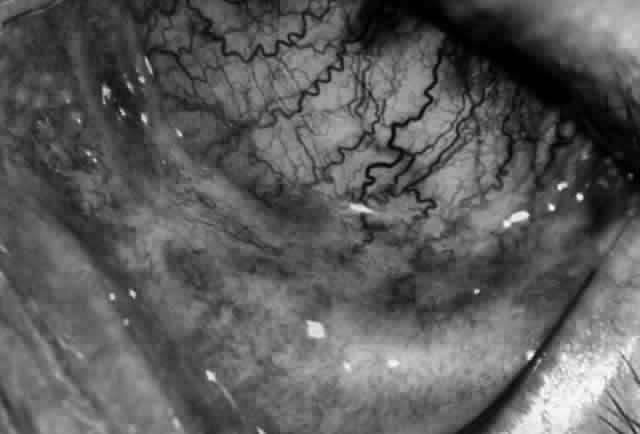

Clinically, the ocular disease in cicatricial pemphigoid (OCP) may present unilaterally in the form of a chronic, recurrent catarrhal conjunctivitis, but it eventually becomes bilateral. Subepithelial fibrosis is characteristic of stage 1 of OCP (Fig. 7). Stage 2 shows fornix foreshortening (Fig. 8), and symblepharon formation is the hallmark of stage 3 (Fig. 9). Stage 4, end-stage disease, is characterized by ankyloblepharon and surface keratinization (Fig. 10). Obstruction of the lacrimal ductules and meibomian gland ducts eventually produces an unstable tear film and progressive sicca syndrome, but it is to be emphasized that OCP is not a dry-eye syndrome until late in the disease course.20 Trichiasis and entropion occur because of the subepithelial fibrosis, with eventual keratopathy, corneal neovascularization, and corneal ulceration and scarring.20

Fig. 7. Stage 1 cicatricial pemphigoid, with cicatrizing conjunctivitis, and fine striae-type areas of subepithelial fibrosis, but without evidence of shrinkage of the conjunctiva.

Fig. 8. Stage 2 cicatricial pemphigoid, with fornix foreshortening and subepithelial fibrosis without frank symblepharon formation.

Fig. 9. Stage 3 of an eye affected by cicatricial pemphigoid. The conjunctival “shrinkage” continued and a frank symblepharon developed.

Fig. 10. Stage 4 cicatricial pemphigoid. Progressive shrinkage of the conjunctiva resulted in extreme trichiasis and distichiasis and keratopathy, with compromise of meibomian ductules and lacrimal ductules and the production of a totally dry eye.